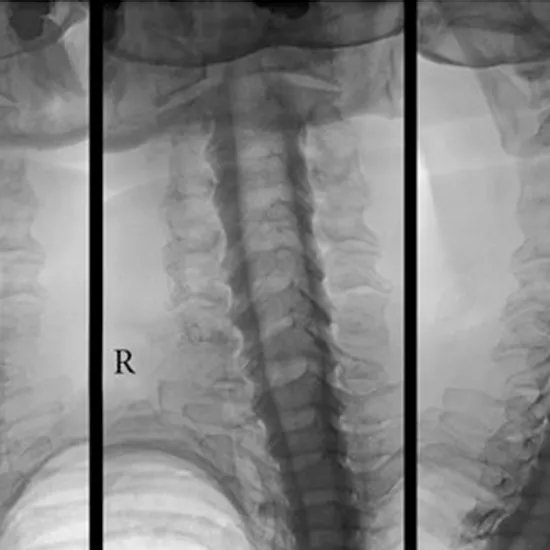

X-Ray Myelogram

A myelogram is an X-ray test that lets specialists see the spinal cord and the area around it. It helps find problems with the spinal canal, the lining of the canal, and the nerve roots.